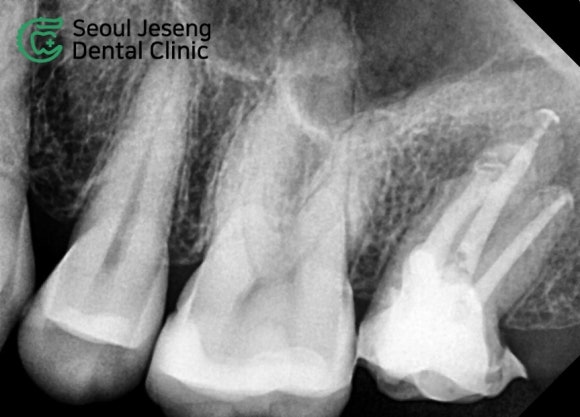

사진상 오른쪽 위에 보이는 치아입니다.

노란 점선 안에 있는 치아에 주목해주세요.

신경치료용 CT를 촬영하니 상악동으로 염증이 파급되려는 상태였고, 기존 신경치료의 흔적도 확인할 수 있었습니다.

치아를 감싸는 뼈를 치조골이라고 합니다.

윗 어금니의 치조골은, 해부학적인 구조 상 상악동에 인접합니다.

위 사진에서는 치아에서 시작된 염증이 치조골을 녹이고, 이어서 상악동까지 침범하려고 하는 소견이 관찰됩니다.

상악동까지 침범된 염증은 재빠르게 해결해주어야 합니다.

방치될 경우 상악동염(=부비동염=축농증)으로까지 이어질 수 있기 때문입니다.